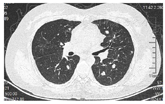

2019年12月5日—2020年2月13日行盆腔外照射(CTV 45 Gy/25 f,CTV 60 Gy/25 f)+阴道近距离放疗6 Gy×5 f,外照射放疗区域包括全子宫,全阴道,骨转移区,腹膜后、盆腔、腹股沟淋巴引流区,放疗期间行同步顺铂50 mg化疗6次。患者放疗及同步化疗结束后阴道穹窿及阴道前壁上1/3仍有残留病灶,建议患者补充全身静脉化疗,患者因自身对生活治疗要求高,坚决拒绝化疗。患者病理检测提示PD-L1阳性(CPS≥1),根据2020年NCCN指南及国内外临床试验PD-1抑制剂治疗推荐用于PD-L1表达阳性或MSI-H/d MMR表达的晚期宫颈癌的治疗,2020年3月13日—2020年9月1日行卡瑞丽珠单抗注射液200 mg,每2周1次,静脉滴注治疗,同时联合唑来磷酸抑制骨破坏。患者2020年7月30日使用卡瑞丽珠单抗10个疗程治疗后出现咳嗽,患者呼吸科就诊,口服止咳药及头孢抗炎治疗后咳嗽症状好转,无呼吸困难及气喘及气短症状,2020年8月14日完善胸部CT提示双肺多叶段新增多发斑片磨玻璃密度影,感染性病变?(图2A),结合患者病史及CT检查考虑为肺部感染可能性大,不除外免疫检查点抑制剂相关性肺炎,需密切监测患者症状及影像学检查。2020年8月16日行第11个疗程治疗后仍有咳嗽,但较前无明显加重,继续抗炎止咳治疗。2020年8月31日复查胸部CT提示双肺多叶段多发斑片磨玻璃密度影范围大致同前,部分密度较前增高,感染性病变?余胸部所见基本同前(图2B)。2020年9月1日行第12个疗程治疗,治疗后2 d患者出现气喘,进行性加重,治疗后7 d患者出现无明显自主咳嗽症状,刺激性气味可诱发咳嗽症状,不伴咳痰,静息状态下气喘尚可,体力活动后气喘加重,伴气短及呼吸困难,休息后可缓解,考虑患者为免疫检查点抑制剂相关性肺炎,遂急诊返院。2020年9月10日胸部CT提示双肺多叶、段模糊磨玻璃密度斑片影范围较前增多,请结合临床注意血管炎,药物性肺损伤?余胸部所见基本同前(图2C)。肺弥散功能提示肺总弥散量重度下降,单位弥散量轻度下降。肺通气功能提示重度混合性通气功能障碍,限制为主。免疫检查点抑制剂相关性肺炎美国国家综合癌症网(National Comprehensive Cancer Network,NCCN)指南[2]以临床结合影像学进行分级。具体标准:1级,无症状,病变局限于一叶肺或病变范围<25%的肺实质;2级,出现新的呼吸道症状或原有症状加重,包括气短、咳嗽、胸痛、发热,以及所需吸氧条件升高;3级,症状严重,病变累及所有肺叶或>50%肺实质,日常活动受限;4级,危及生命的呼吸损害。患者胸部CT提示双肺多叶、段模糊磨玻璃密度斑片影范围较前增多,病变累及部位>50%肺实质,结合患者症状诊断为免疫检查点抑制剂相关肺炎3级。

患者诊断为免疫检查点抑制剂相关性肺炎3级,根据《CSCO免疫检查点抑制剂相关肺炎的临床诊治建议》,对于2~3级的CIP,推荐使用1~2 mg/(kg·d)泼尼松的等效剂量激素治疗,可选择口服或静脉激素(泼尼松或甲泼尼龙),对于更严重者或急性病程者,首选静脉激素。对于激素的减量方法,推荐在观察到起始剂量[1~2 mg/(kg·d)]激素起效后(48~72 h),继续维持原剂量使用至7~14 d,随后开始逐步减量,控制整体疗程在6~8周,一般不超过12周。足量激素治疗时间建议最长不超过3周[3]。激素使用过程中需要注意监测相应的毒副作用。患者体重为65 kg,推荐使用65~130 mg泼尼松的等效剂量激素治疗,患者2020年9月11日—2020年9月13日甲泼尼龙注射液80 mg静脉输液治疗,患者症状明显缓解,无呼吸困难,活动后无明显气短,可自行上下楼梯,因患者较年轻,现放疗后人工绝经,患者及家属非常担忧骨质疏松,股骨头坏死等副作用,要求激素减量,2020年9月14日—2020年9月16日予甲泼尼龙注射液60 mg静脉输液治疗,2020年9月17日—2020年9月19日予甲泼尼龙注射液40mg静脉输液治疗,患者已无免疫检查点抑制剂相关性肺炎症状,改为口服激素治疗,2020年9月20日—2020年9月23日予美卓乐(甲泼尼龙片)8片口服(32 mg=泼尼松的等效剂量40 mg)治疗,2020年9月24日—2020年9月30日予美卓乐6片口服(24 mg=泼尼松的等效剂量30 mg),2020年10月1日—2020年10月7日予美卓乐4片口服(16 mg=泼尼松的等效剂量20 mg),2020年10月8日—2020年10月14日予美卓乐2片口服(8 mg=泼尼松的等效剂量10 mg),2020年10月15日—2020年10月21日予美卓乐2片口服(4 mg=泼尼松的等效剂量5 mg),共使用糖皮质激素治疗6周。其间复查胸部CT模糊斑片影较前明显缓解(图3)。糖皮质激素治疗期间予患者补充钙剂、维生素D3,骨化醇预防骨质疏松,质子泵抑制剂,膜固思达,洁维乐保护胃肠道黏膜,预防应激性溃疡。同时监测感染相关指标,监测血压、血糖、电解质等,患者大便真菌涂片及咽真菌涂片找到真菌孢子,予使用大扶康抗真菌感染治疗。

患者糖皮质激素停药后8 d,2020年10月29日患者再次出现胸部不适,通气不畅,吸入冷空气可诱发咳嗽,1 d后再次出现行走后呼吸费力及胸痛,患者急诊返院。完善胸部CT提示双肺多叶、段磨玻璃密度斑片影范围较前增大、密度较前增高(图4)。患者已完成糖皮质激素治疗,停药后再次出现目前免疫检查点抑制剂相关肺炎症状,因患者病情复杂,完善多学科疑难病例会诊,影像科会诊意见患者目前CT提示肺部以对称性、渗出性病变为主,纤维化不重,暂无间质性改变。此种肺部影像学变化常为过敏反应,药物反应及肺水肿,此患者考虑与药物性肺炎有关。目前患者病情反弹,考虑激素依赖,建议密切复查肺部HRCT。呼吸科会诊意见考虑免疫治疗相关肺不良反应可能性大,不除外过敏性肺泡炎。建议停用免疫治疗,复查总IGE及过敏原检查,变态反应原除外过敏反应。患者目前症状反复与糖皮质激素剂量有关,可适当延长糖皮质激素使用时间,建议复查结核相关检查。感染科会诊意见患者目前CRP、降钙素原不高,COVID19核酸多次监测阴性,不考虑细菌性肺炎,可行巨细胞病毒IGm、IGg,病毒载量及EBV病毒IGm、IGg,病毒载量检查及呼吸道病毒检测(痰液)除外病毒性感染,风湿科会诊意见密切复查肺CT,找到合适激素剂量维持,不除外药物反应,如药物延迟超敏反应。如患者症状持续进展,建议可上级医院会诊治疗,建议完善铁蛋白,总IgE,ANA,红细胞沉降率,大小系列,白介素,淋巴计数等检查。患者上述检查均无明显异常,综合会诊意见,考虑患者症状再发原因是激素依赖型,既往激素治疗过程中激素减量较快,继续予患者糖皮质激素治疗,此次需延长糖皮质激素治疗时间,缓慢减少糖皮质激素用量。2020年10月30日—2020年11月5日予美卓乐8片口服(32 mg=泼尼松的等效剂量40 mg),2020年11月6日—2020年11月12日予美卓乐6片口服(24 mg=泼尼松的等效剂量30 mg),2020年11月13日—2020年11月19日予美卓乐5片口服(20 mg=泼尼松的等效剂量25 mg),2020年11月20日—2020年11月26日予美卓乐4片口服(16 mg=泼尼松的等效剂量20 mg),2020年11月27日—2020年12月3日予美卓乐3片口服(12 mg=泼尼松的等效剂量15 mg),2020年12月4日—2020年12月10日予美卓乐3片与2片交替口服,2020年12月11日—2020年12月17日予美卓乐2片口服(8 mg=泼尼松的等效剂量10 mg),2020年12月18日—2020年12月24日予美卓乐2片与1片交替口服,2020年12月25日—2021年1月7日予美卓乐1片口服(4 mg=泼尼松的等效剂量5 mg),本次共使用糖皮质激素治疗10周。患者第2次糖皮质激素治疗后出现较严重副作用,包括水潴留,周身水肿,激素患者减量至美卓乐1片时患者仍需利尿剂治疗,皮质功能亢进综合征,体重增加(由激素治疗前65 kg增至68 kg),腹泻(诺如病毒感染)及便真菌感染,均予对症治疗。

患者的第2次激素治疗后症状完全缓解,复查胸部CT肺部斑片影基本消失(图4)。第2次激素停药后长期随访无再发免疫检查点抑制剂相关性肺炎症状,免疫检查点抑制剂相关性肺炎治愈。